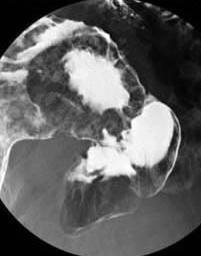

Radiologie de cancer de

estomac . Image en bourgeon . Aspect de type 2 |

Ulceration maligne avec

bourrelet sur eleve |